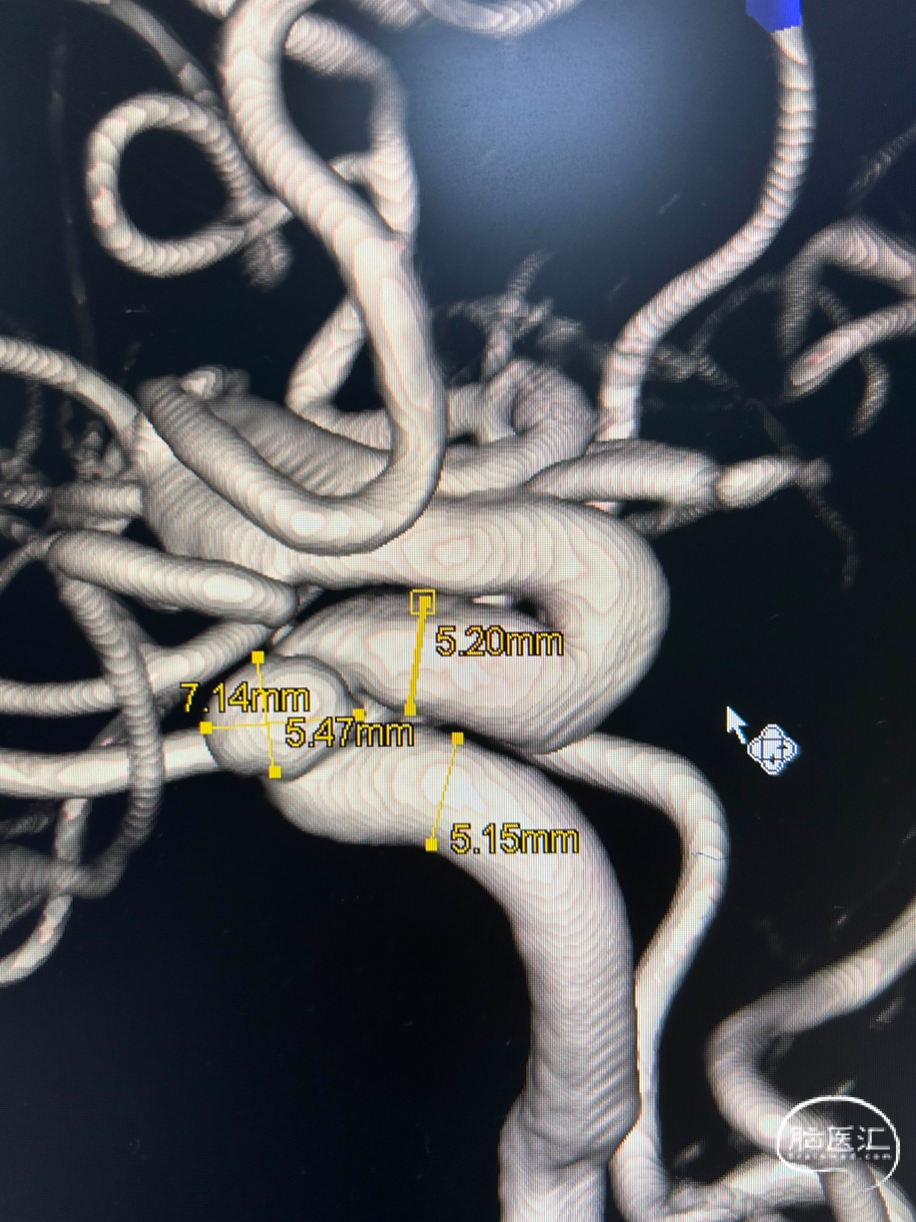

术前造影—3D

DSA:左侧颈内动脉C4段动脉瘤,大小约7.14*5.47mm,瘤颈宽约5.5mm。